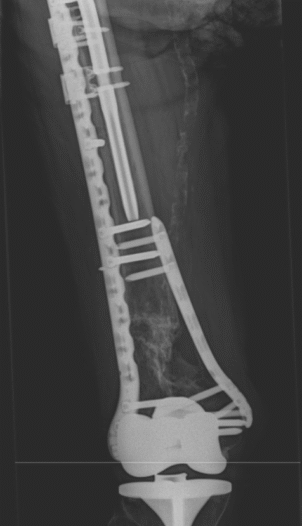

Entre sus áreas de especialización, se encuentran el tratamiento de fracturas complejas, la cirugía de pelvis y acetábulo mínimamente invasiva y la reconstrucción ósea con fijadores circulares para el tratamiento de pseudoartrosis e infecciones.

Ocurre cuando una fractura no sana correctamente o tarda más de lo esperado en curar.